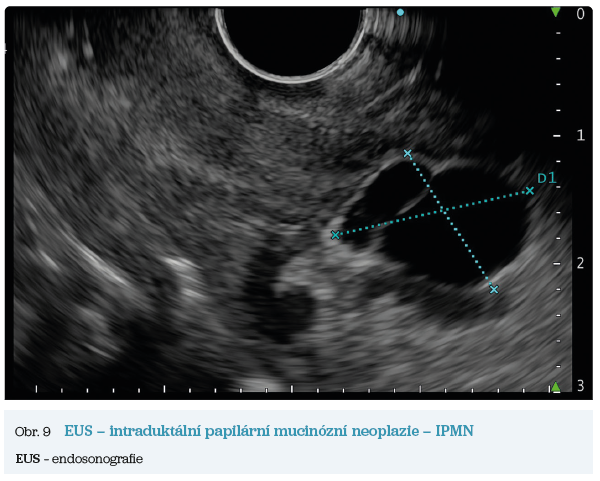

EUS umožňuje přesné vyšetření pankreatu. Lze také identifikovat a vyšetřit regionální lymfatické uzliny a vztah pankreatických lézí k okolním cévním strukturám. EUS může také sloužit jako navigace k odběru bioptického materiálu k cytologickému a histologickému vyšetření.21 AI je zde využívána k potvrzení malignity v IPMN. Kuwahara a kol. dosáhli s využitím 3 970 snímků a CNN algoritmu velké úspěšnosti v diferenciaci benigní a maligní IPMN s AUC 0,98.22 Řada studií se již zabývala AI asistovaným rozlišením chronické pankreatitidy a karcinomu pankreatu s AUC 0,940–0,986.23,24 Velká studie obsahující 1 174 461 snímků z celkem 583 případů hodnotící rozlišení autoimunitní pankreatitidy, karcinomu pankreatu, chronické pankreatitidy a normálního pankreatu dosáhla pro karcinom pankreatu AUC 0,97625 (obr. 6–9).